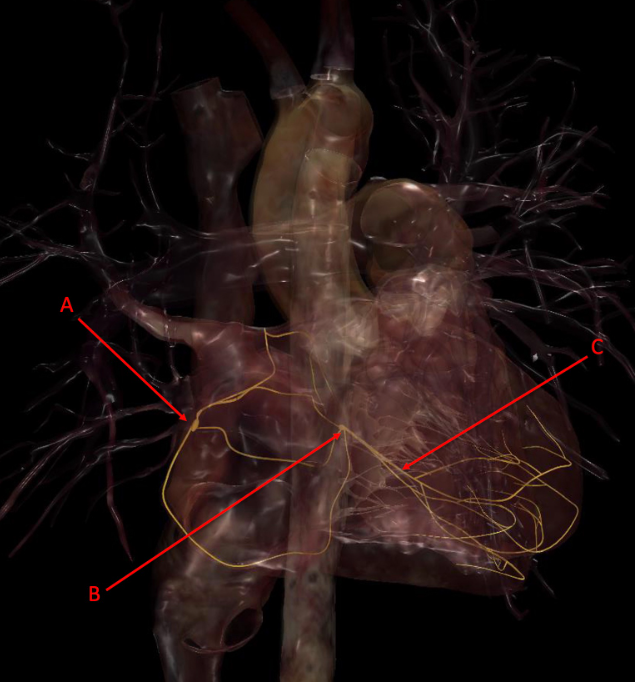

A. anterior interventricular artery

B. left circumflex artery

C. marginal or posterior interventricular artery